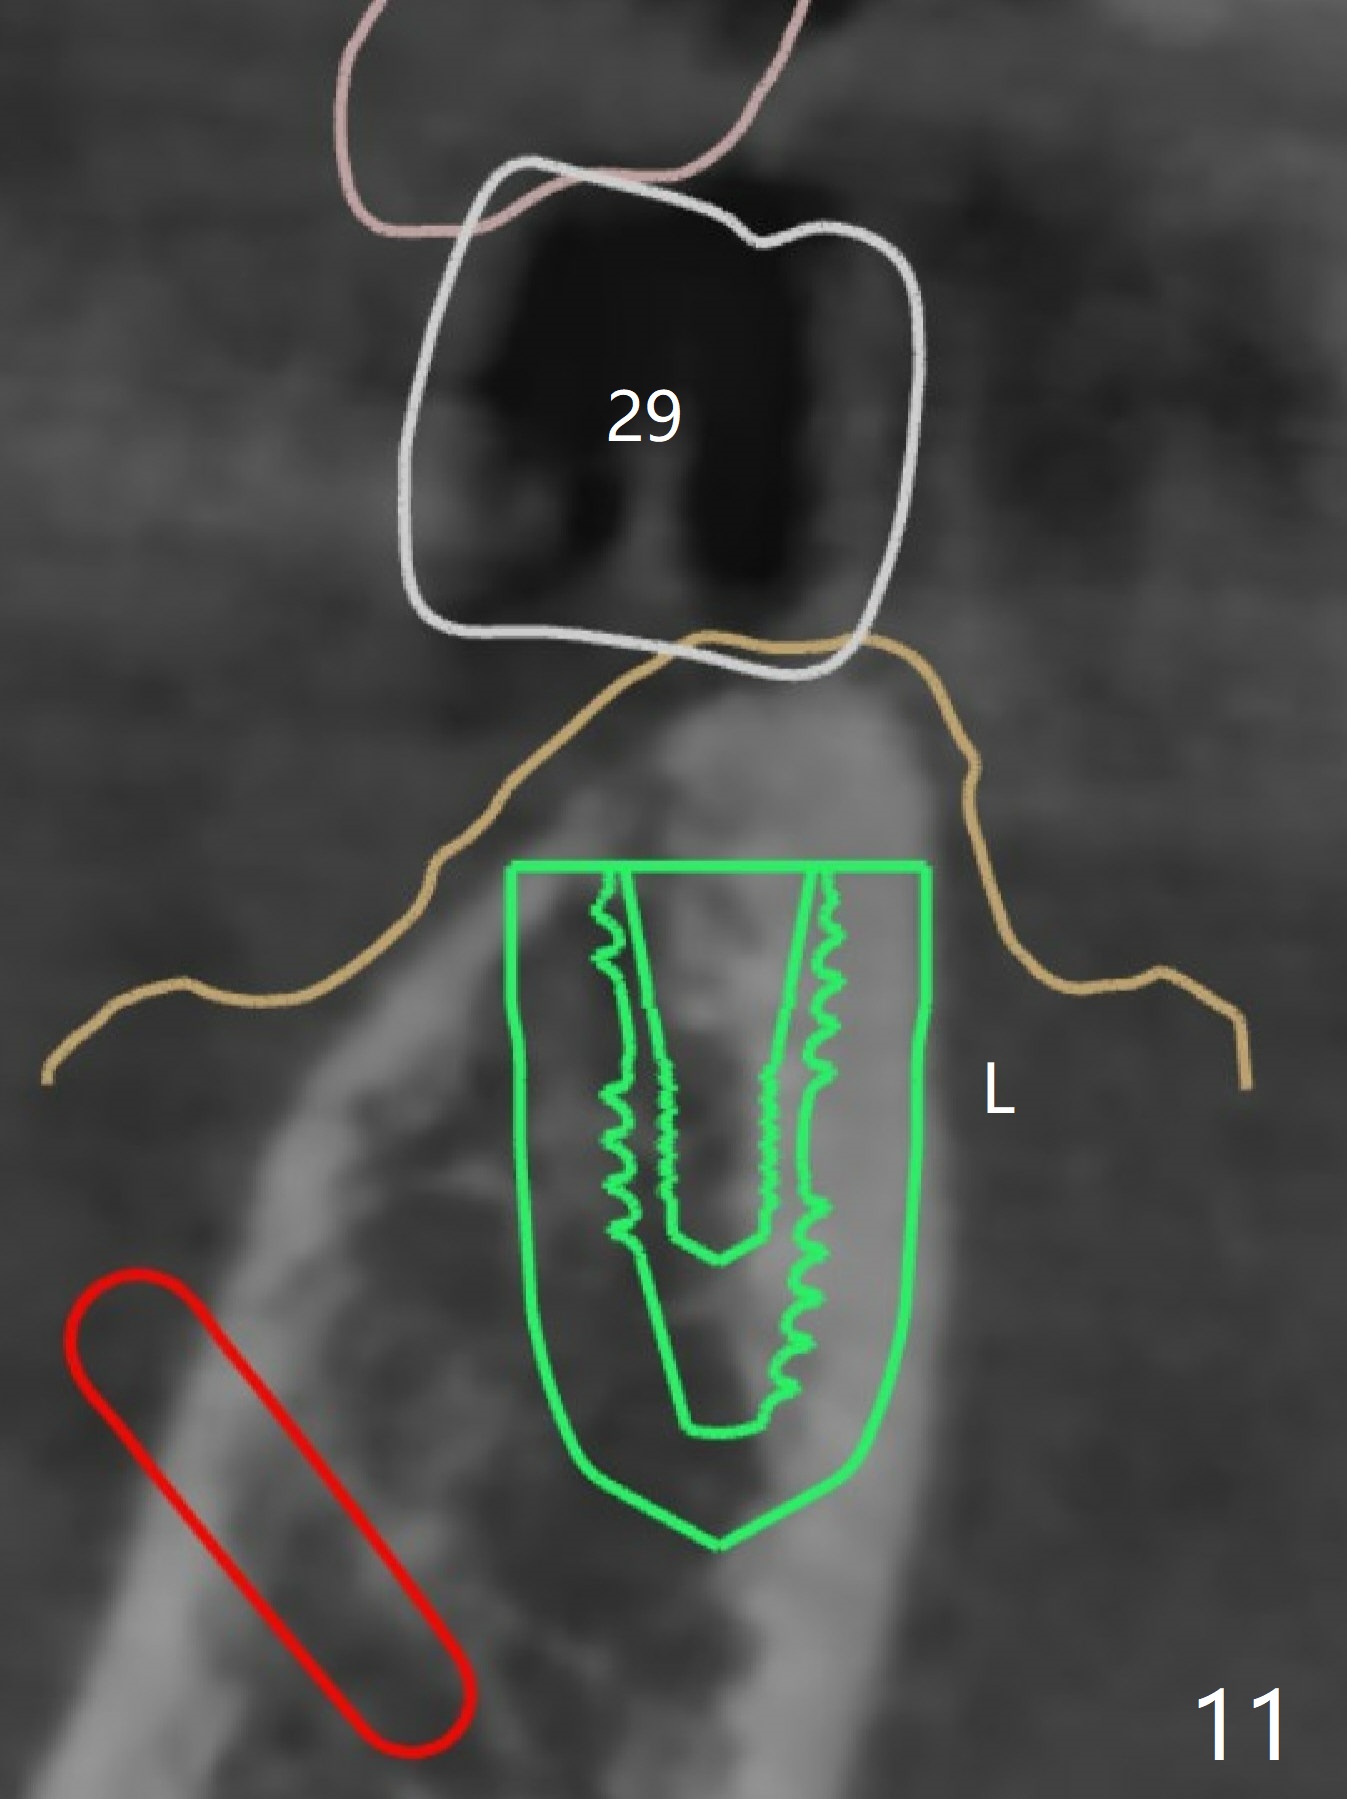

The extraction socket of #31 has a thin septum (Fig.2), which is removed partially with 12 mm bone trimmer (Fig.3). After placement of a 5x9 mm FC implant (~40 Ncm) and 6 mm bone profile drill, a 5.5x4(2) mm abutment is incompletely seated (Fig.5 <) and later is changed to a 4.5x1 mm temporary abutment (Fig.6, 8 T). The latter is used to fabricate a provisional, which in turn supports the distal papilla (Fig.8 *). The gingiva is slightly erythematous immediately post periodontal dressing removal (3 weeks postop, Fig.9). Take CT to confirm whether the cortical drill helps keep the #29 implant lingual. Use a profile drill at #29 if crestal bone loss is not obvious. There is bone coronal to #29 implant 4 months postop (Fig.10). Upon incision, the ridge is rounded (Fig.10'), but the implant appears to be buccally placed (Fig.10'' (post high speed handpiece and 5.5 mm profile drill)). The latter is confirmed by CT (Fig.12, as compared to design (Fig.11)). In spite of use of cortical drill coronally, the implant is still deviated buccally due to contrasting deferential bone density linguobuccally (Fig.13). By comparison, there is no such bone density differential involving an immediate implant at #31; the implant is placed in the socket without contacting the buccal or lingual cortices (Fig.14). The final implant is the same as expected (Fig.15). To avoid implant deviation in the lower premolar region, leave the root in place until osteotomy is finished. Five months postop, the temporary and healing abutments at #31 and 29 change to pair ones (Fig.16). Since there is limited clearance from the crestal bone, smaller abutments are used with the apparently same degree of seating (Fig.17). The abutments are prepared due to the mesial (#31) and buccal (29) tilt before impression.